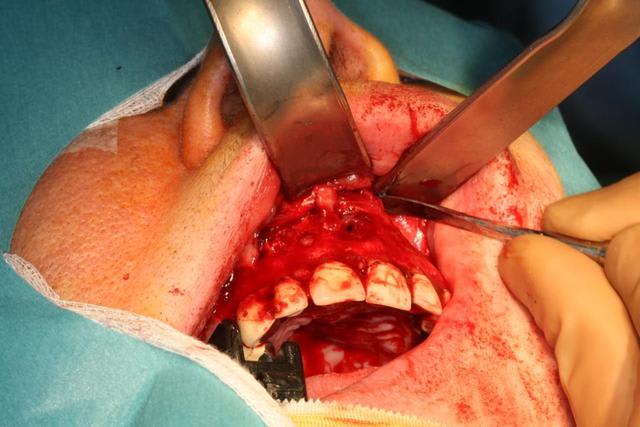

Ce matin j'ai opéré une patiente pour un bon kyste maxillaire d'origine dentaire très certainement et quelques petits sur d'autres dents.

Dans un premier temps j'ai disséqué le kyste qui a détruit le plancher des fosses nasales et le mur palatin.

Dans un second temps j'ai fait des préparations à rétro sur les dents causales (11-21-22-14). Puis j'ai réalisé un collage à rétro car les tenons atteignaient les apex.

Enfin j'ai isolé par des membranes Biogide et comblé avec du bétaTCP.